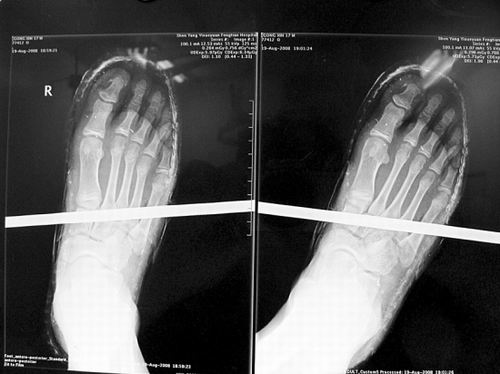

事发时男孩穿着一双布鞋,骨外二科陈宾医生操起剪刀,将布鞋一块块剪掉。经X光透视,医生惊奇地发现:男孩虽然被钢筋穿透了右脚,但骨头、大的血管和神经都没受任何伤害!

20日,记者从X光片子上看到,钢筋避开了男孩脚掌骨头密集的部位,而是从脚弓处穿过,这个部位基本上以软组织为主。“真没想到,太神奇了!”几名医生连声感叹,术中,他们分工合作,小心翼翼地将钢筋取出,并做了引流、清创、包扎。